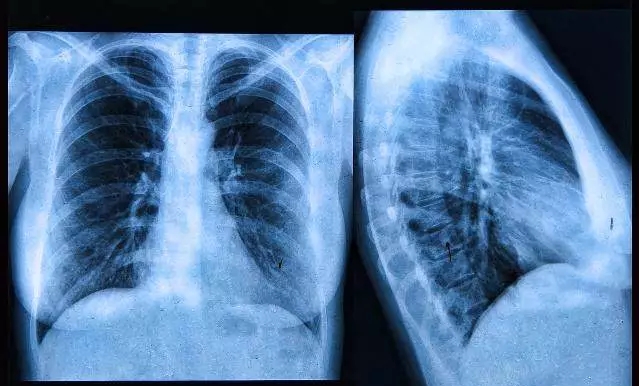

综上有研究表明,长期接触烹调产生的油烟,可能增加 1~2 倍患肺癌的风险。

因此需特别注意!如果经常做饭又出现声音嘶哑、咽喉疼痛、刺激性干咳、痰中带血、咽部有异物,严重时呼吸困难或颈部出现肿块等症状,且此种症状持续一周以上,则要立即去医院就诊!!!